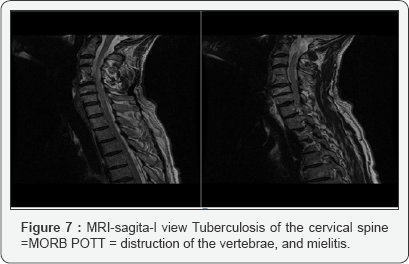

Percutaneous, CT scan guided needle biopsy of bone lesions for anatomo-pathologic studies is very important Biopsy from granulation resulted from surgical drainage of abscesses Microbiologic studies to confirm diagnosis and to isolate organisms for culture and susceptibility. Frequent negative Drainage Some cases of Pott disease are diagnosed following an open drainage procedure (eg, following presentation with acute neurologic deterioration) Figures 6 & 7.

Magnetic resonance imaging

(MRI) is the criterion standard for evaluating disk-space infection and osteomyelitis of the spine and is most effective for demonstrating the extension of disease into soft tissues and the spread of tuberculous debris under the anterior and posterior longitudinal ligaments. . MRI is also the most effective imaging study for demonstrating neural compression.

• Contrast-enhanced MRI findings in Pott disease include thin and smooth enhancement of the abscess wall and a well- defined paraspinal abnormal signal.

• Thick and irregular enhancement of the abscess wall and an ill-defined paraspinal abnormal signal suggest pyogenic spondylitis.

Complications